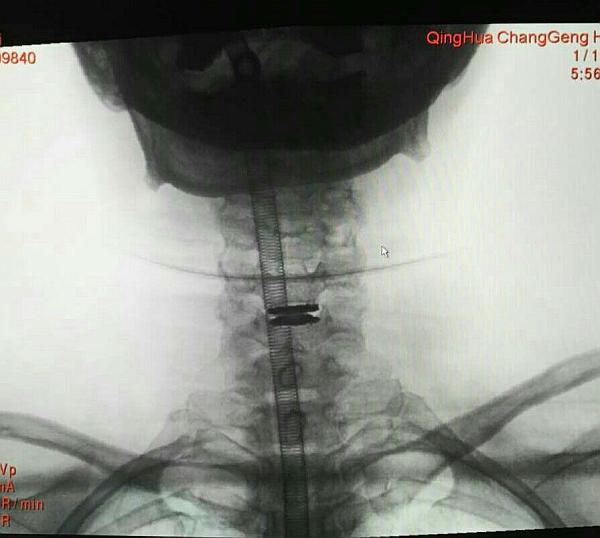

术中O-ARM确定人工椎间盘位置好

手术顺利,手术时间2小时,出血30毫升,术后患者双上肢麻木好转。